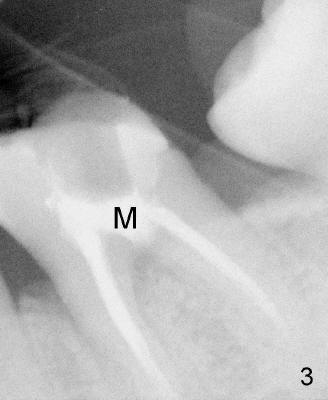

- Perforation can happen in furca (Fig.1: >) between mesial (M) and distal

(D) roots